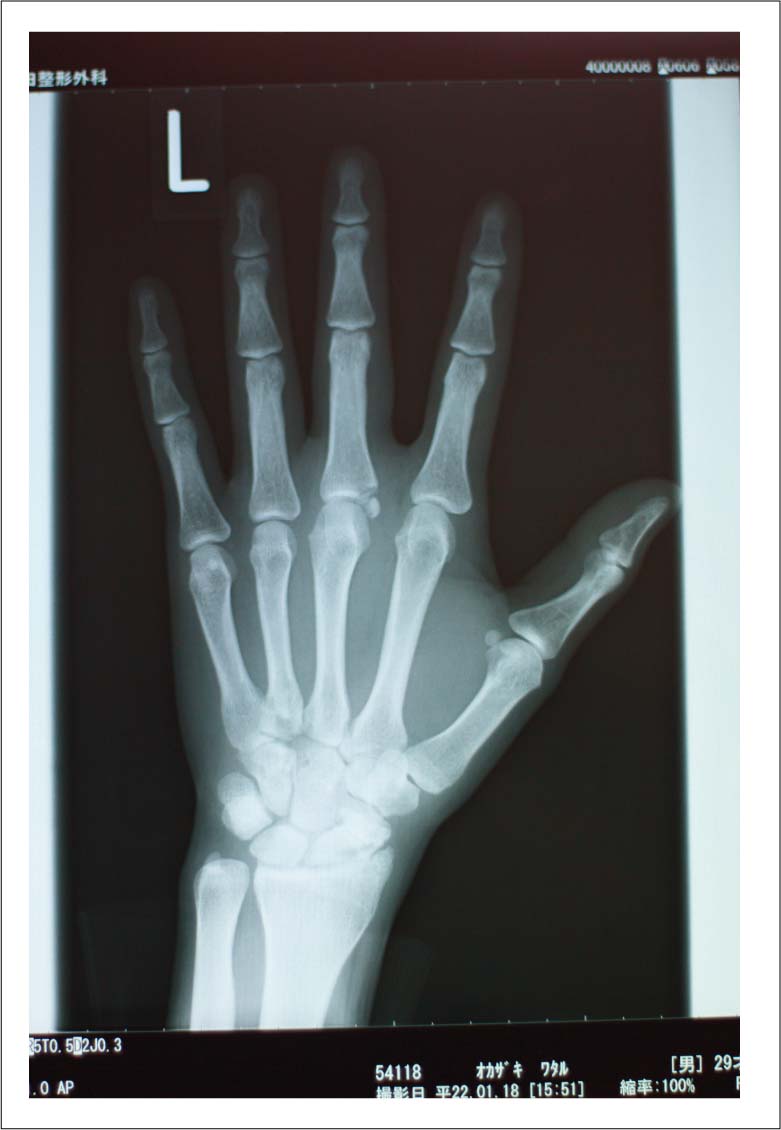

あと、先生がレントゲンをよく見てみると。。。手首も折れてるね〜と言われました。。ヒビみたいのが1センチほど。。。。。

だいぶ昔しに鬼グリッチョした時の写真。。。

靭帯伸ばしてこの先2ヶ月ギプスするハメになる前の状態。。